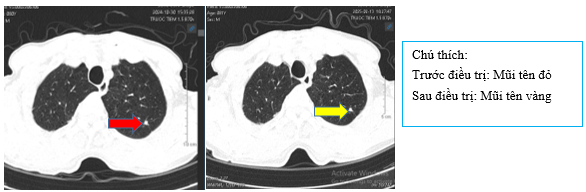

Hình 1:

Hình ảnh chụp CT ngực cho thấyPhổi phải phân thùy S10 có khối ~ 40x30mm bờ tua gai (mũi tên đỏ); thùy trên, thùy dưới còn lại có vài nốt đặc, lớn nhất đường kính 9mm (mũi tên màu cam); Phổi trái: thùy trên có nốt đặc đường kính 3m ngấm thuốc, bờ tua gai (mũi tên xanh lá cây). Nhiều hạch trung thất, lớn nhất ~ 16x12mm (mũi tên xanh dương), có hạch vôi hóa (mũi tên hồng)

+ Chụp CT ngực sau điều trị

Hình 4:

So sánh phim chụp cắt lớp vi tính lồng ngực trước điều trị kích thước khối u thùy dưới phổi phải từ 40x30mm (mũi tên đỏ) sau điều trị giảm còn 26x20mm (mũi tên vàng)